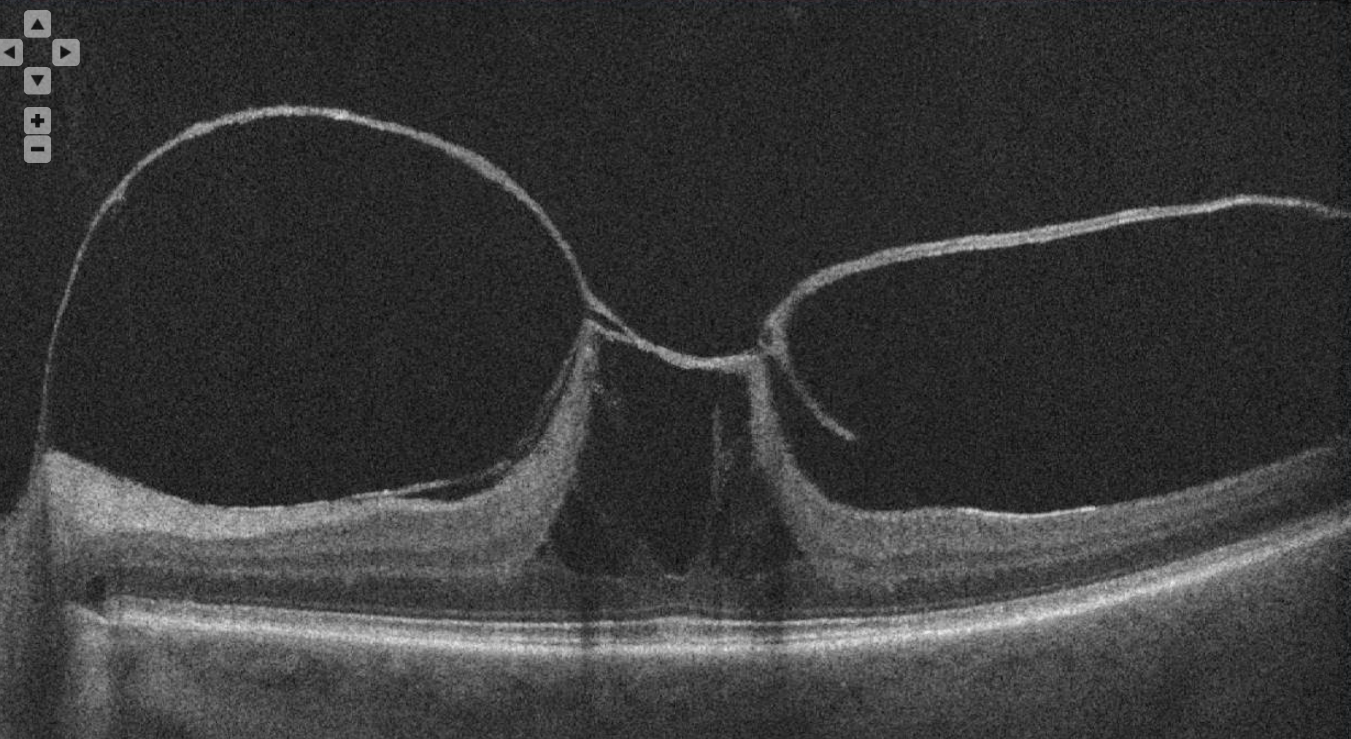

This OCT image shows a retinal condition impacted by the vitreous.

What is VMT?